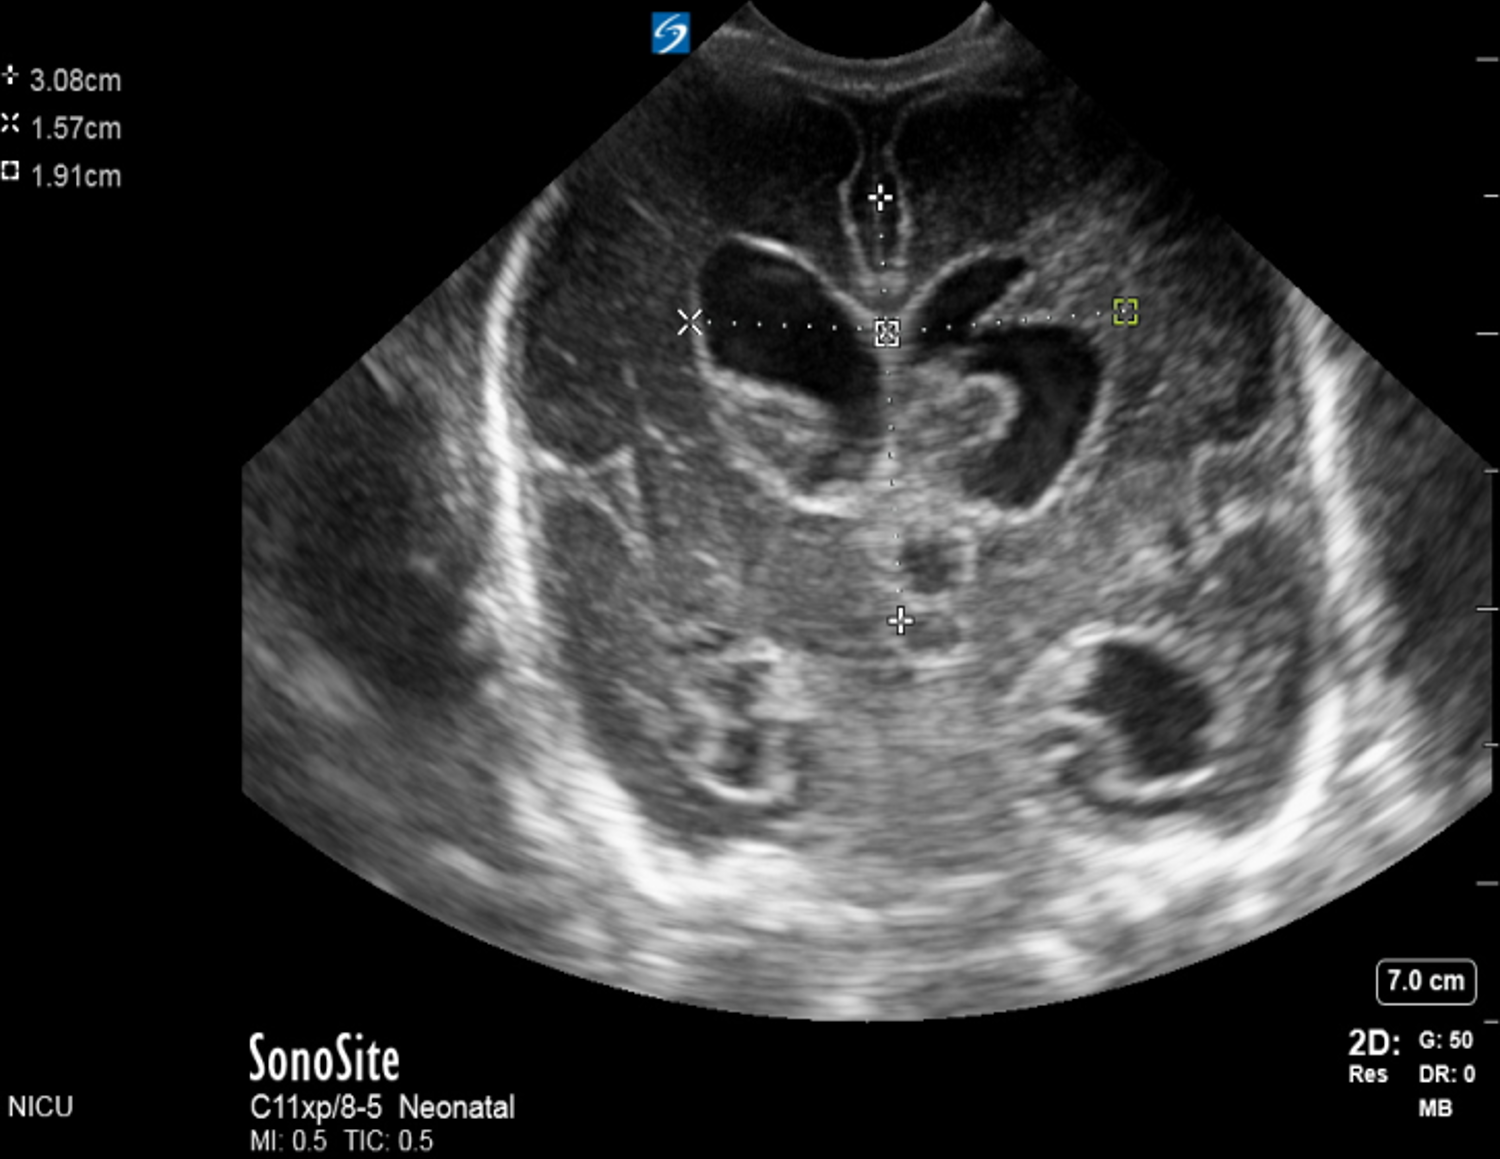

Neonatology Grade 3 IVH Example 1 Image